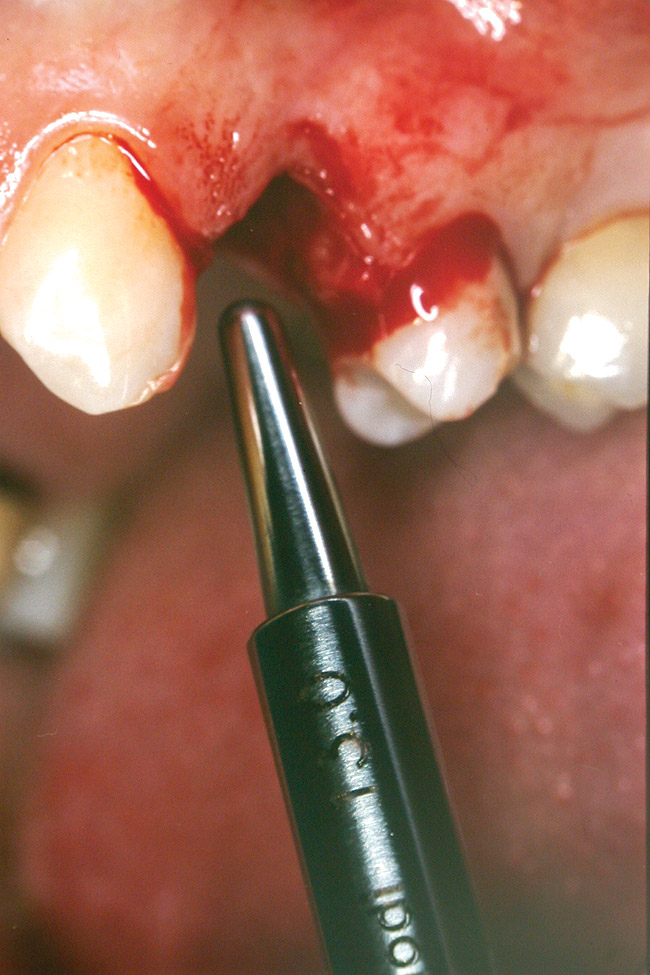

At the time of surgery, local infiltrative anesthesia was administered (lidocaine 2% with epinephrine, 1:100,000). A full-thickness mucoperiosteal flap was raised. The initial osteotomy was performed on midcrestal bone using a rose-headed bur. To prepare the osteotomy site for implant placement, sequential alternating osteotomes with variable conicity were used, drilling 2-mm shorter than the length of the implant to be placed (Figure 3A and Figure 3B). The implants presented initial primary stability (Figure 4), the cover screws were placed, and the implants were submerged for a healing period. The tissue was approximated, and the patient was instructed not to wear any denture or to place pressure on the healing site.

Figure 4  Implant positioning; the radiograph taken 4 weeks after placement confirmed good primary stability.

Figure 4